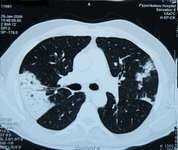

Exploración por TC de tórax de un paciente con toxicidad pulmonar por amiodarona, que muestra opacidades asimétricas con una distribución periférica

De la colección personal del Dr. A. Pataka y el Profesor P. Argyropoulou, Aristotle University, Thessaloniki, Grecia